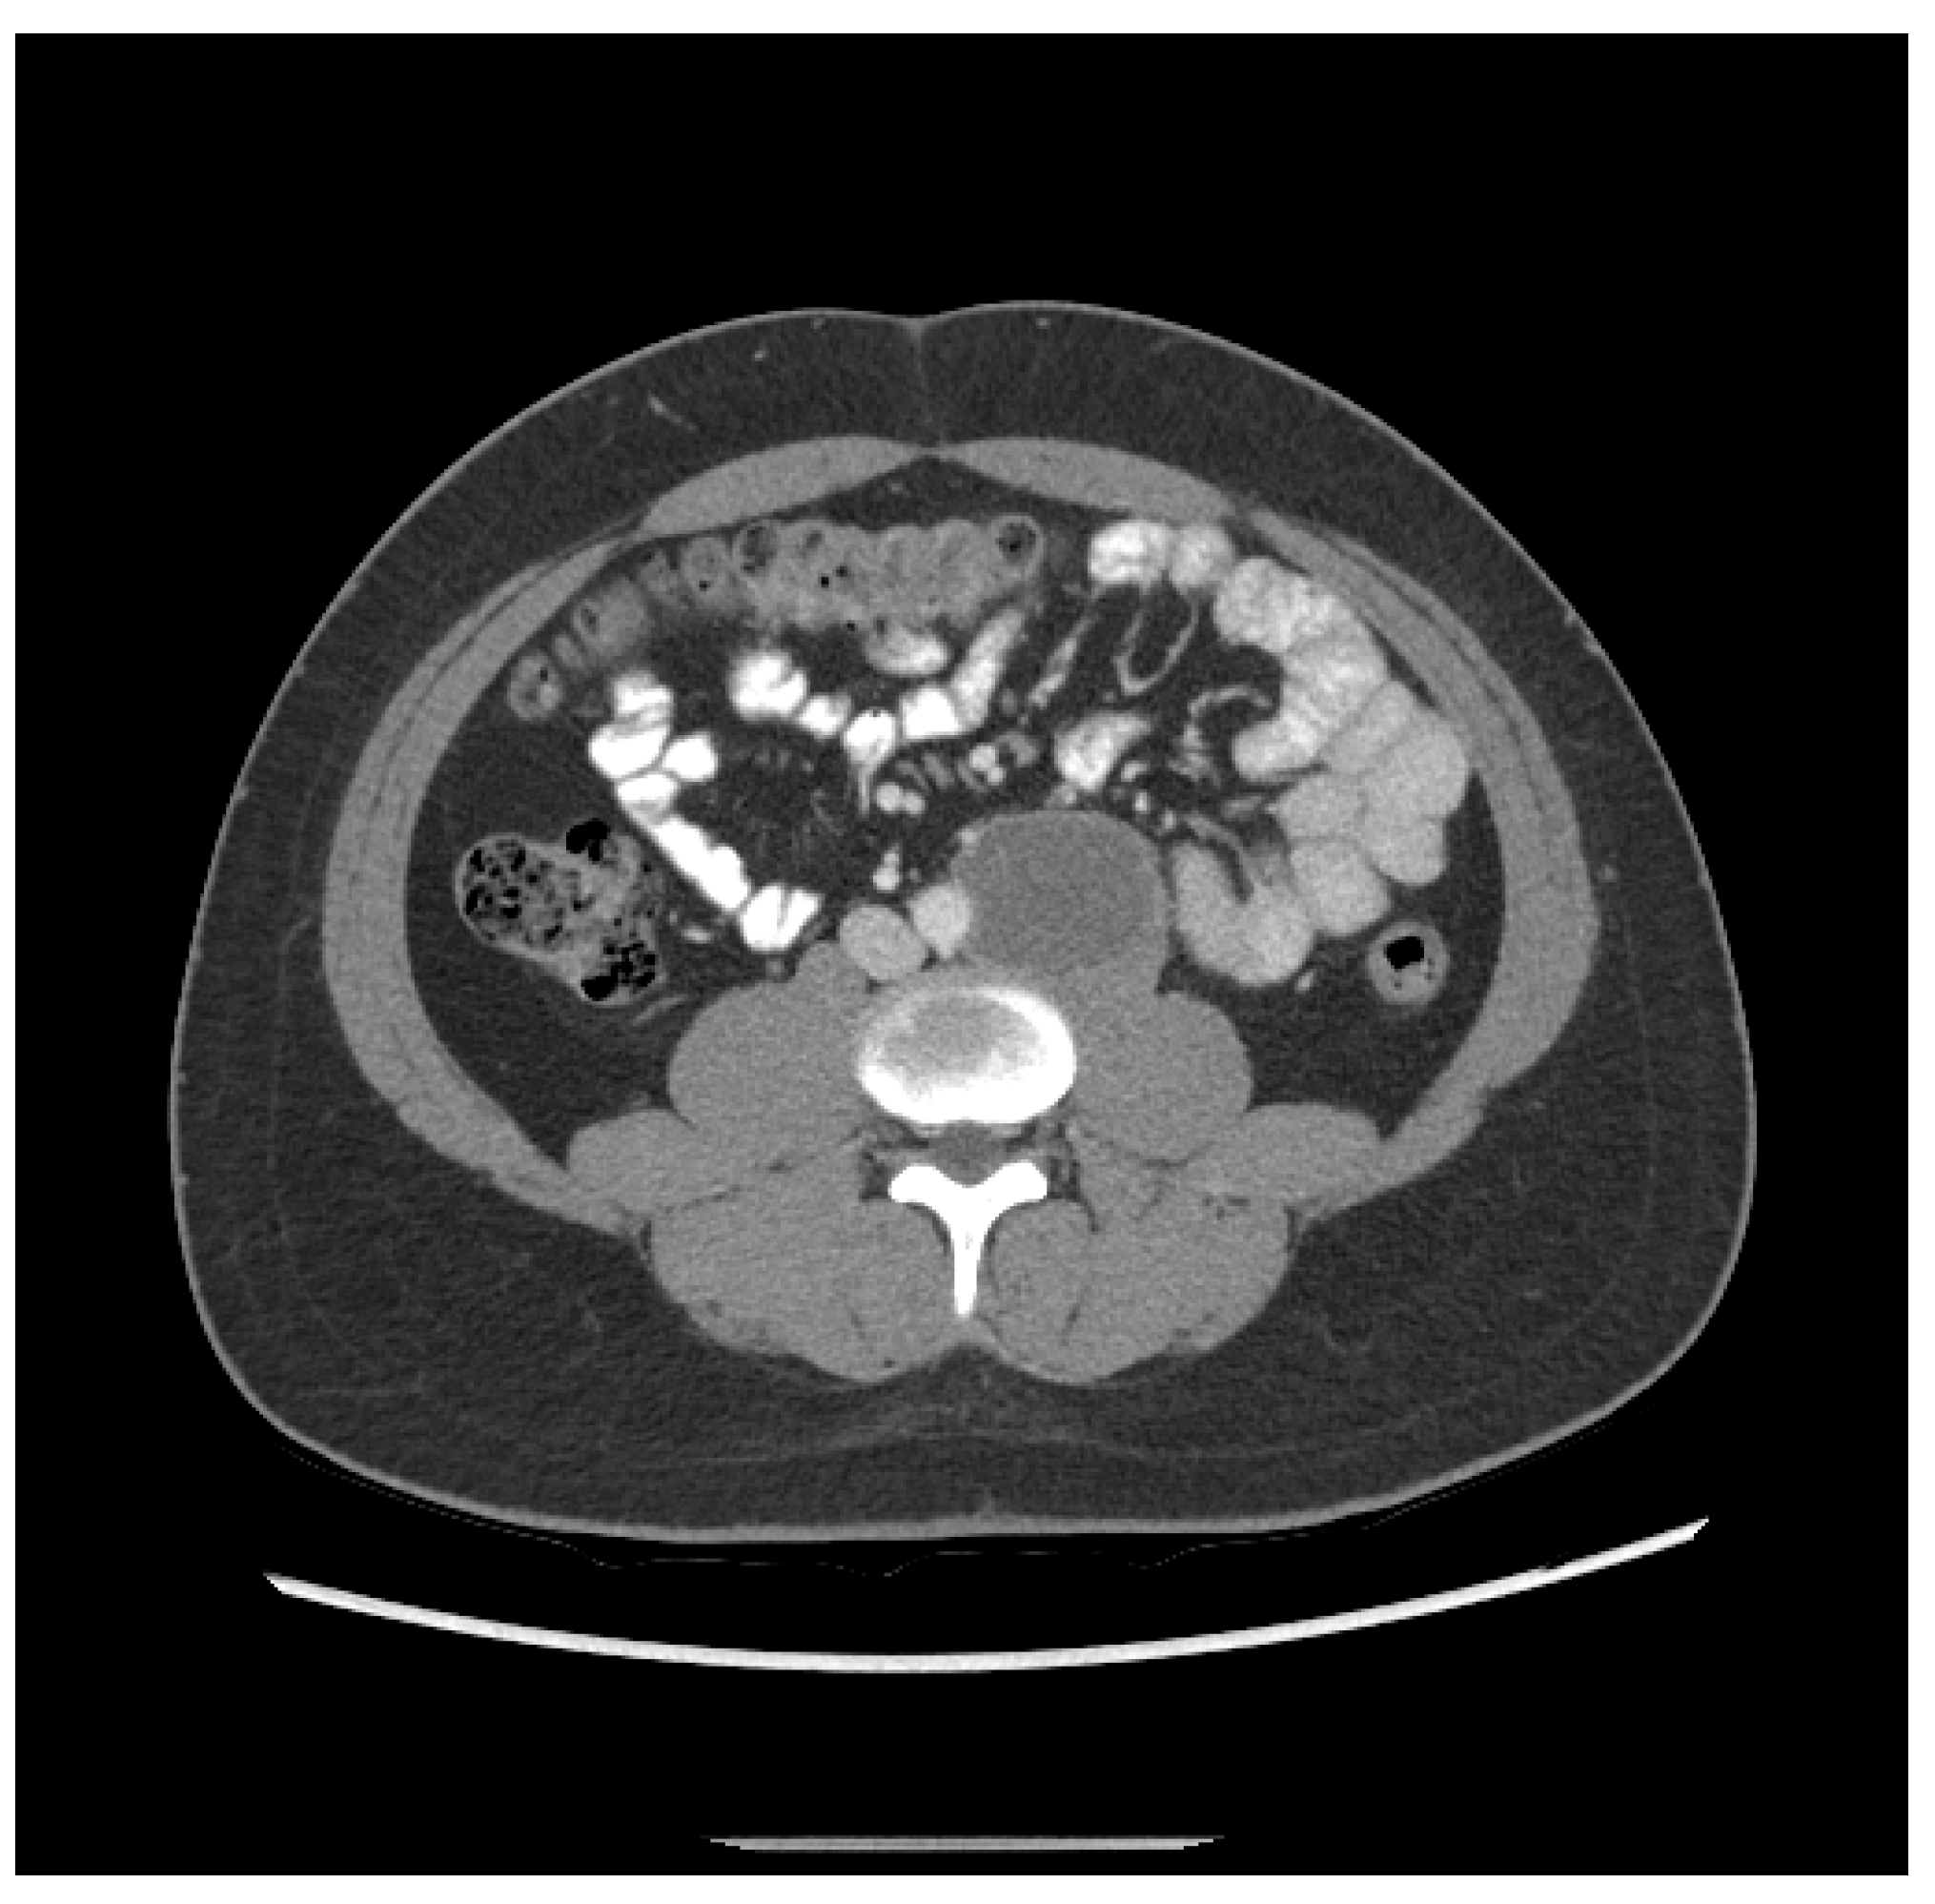

| Patient NSGCT Type | Status | Pathology of Primary | Stage at Time of Diagnosis | S-YSTemic Chemo | Date: Pathology after Chemo |

|---|---|---|---|---|---|

| 1 ETT | Cured | 100% S (elevated AFP) | IIX | BEP x1, VIP x3, paclitaxel (docetaxel), doxorubicin, gemcitabine, | 6/2012: 90% T, 10% ETT + adenocarcinoma |

| 2 S-YST | Cured | 5% E, 90% S, 5% Y | IIIC | BEP x4 | 5/2018, 4/2019, 4/2020: 99% S-YST + 1% T |

| 3 ETT | Cured | 80% ETT, 20% T | IIC | BEP x3 | 1/2018: T w/minute ETT |

| 4 S-YST | Died | NA Y in met | IIIC | BEP x4 | 9/2016: T 1/2021: S-YST |

| 5 ETT | Died | 100% E | IIIA | BEP x1, EP x3, TIP x4, POMB x2, ATP x4, TIP x1/HDC + SCT | 7/2019: Embryonal 11/2019: ETT 1/2020: Choriocarcinoma |

| 6. ETT | Died | 99% E, 1% T | IIIA | BEP x3, TIP x3, ATP | 9/2018: E, C 7/2019, 8/2019: 60% ETT + squamous cell carcinoma |

| 7 S-YST | Died | NA i(12p)+ in met | IIC | BEP x2, XELOX, ATP x2 | 8/2019: S-YST (Unresectable) |